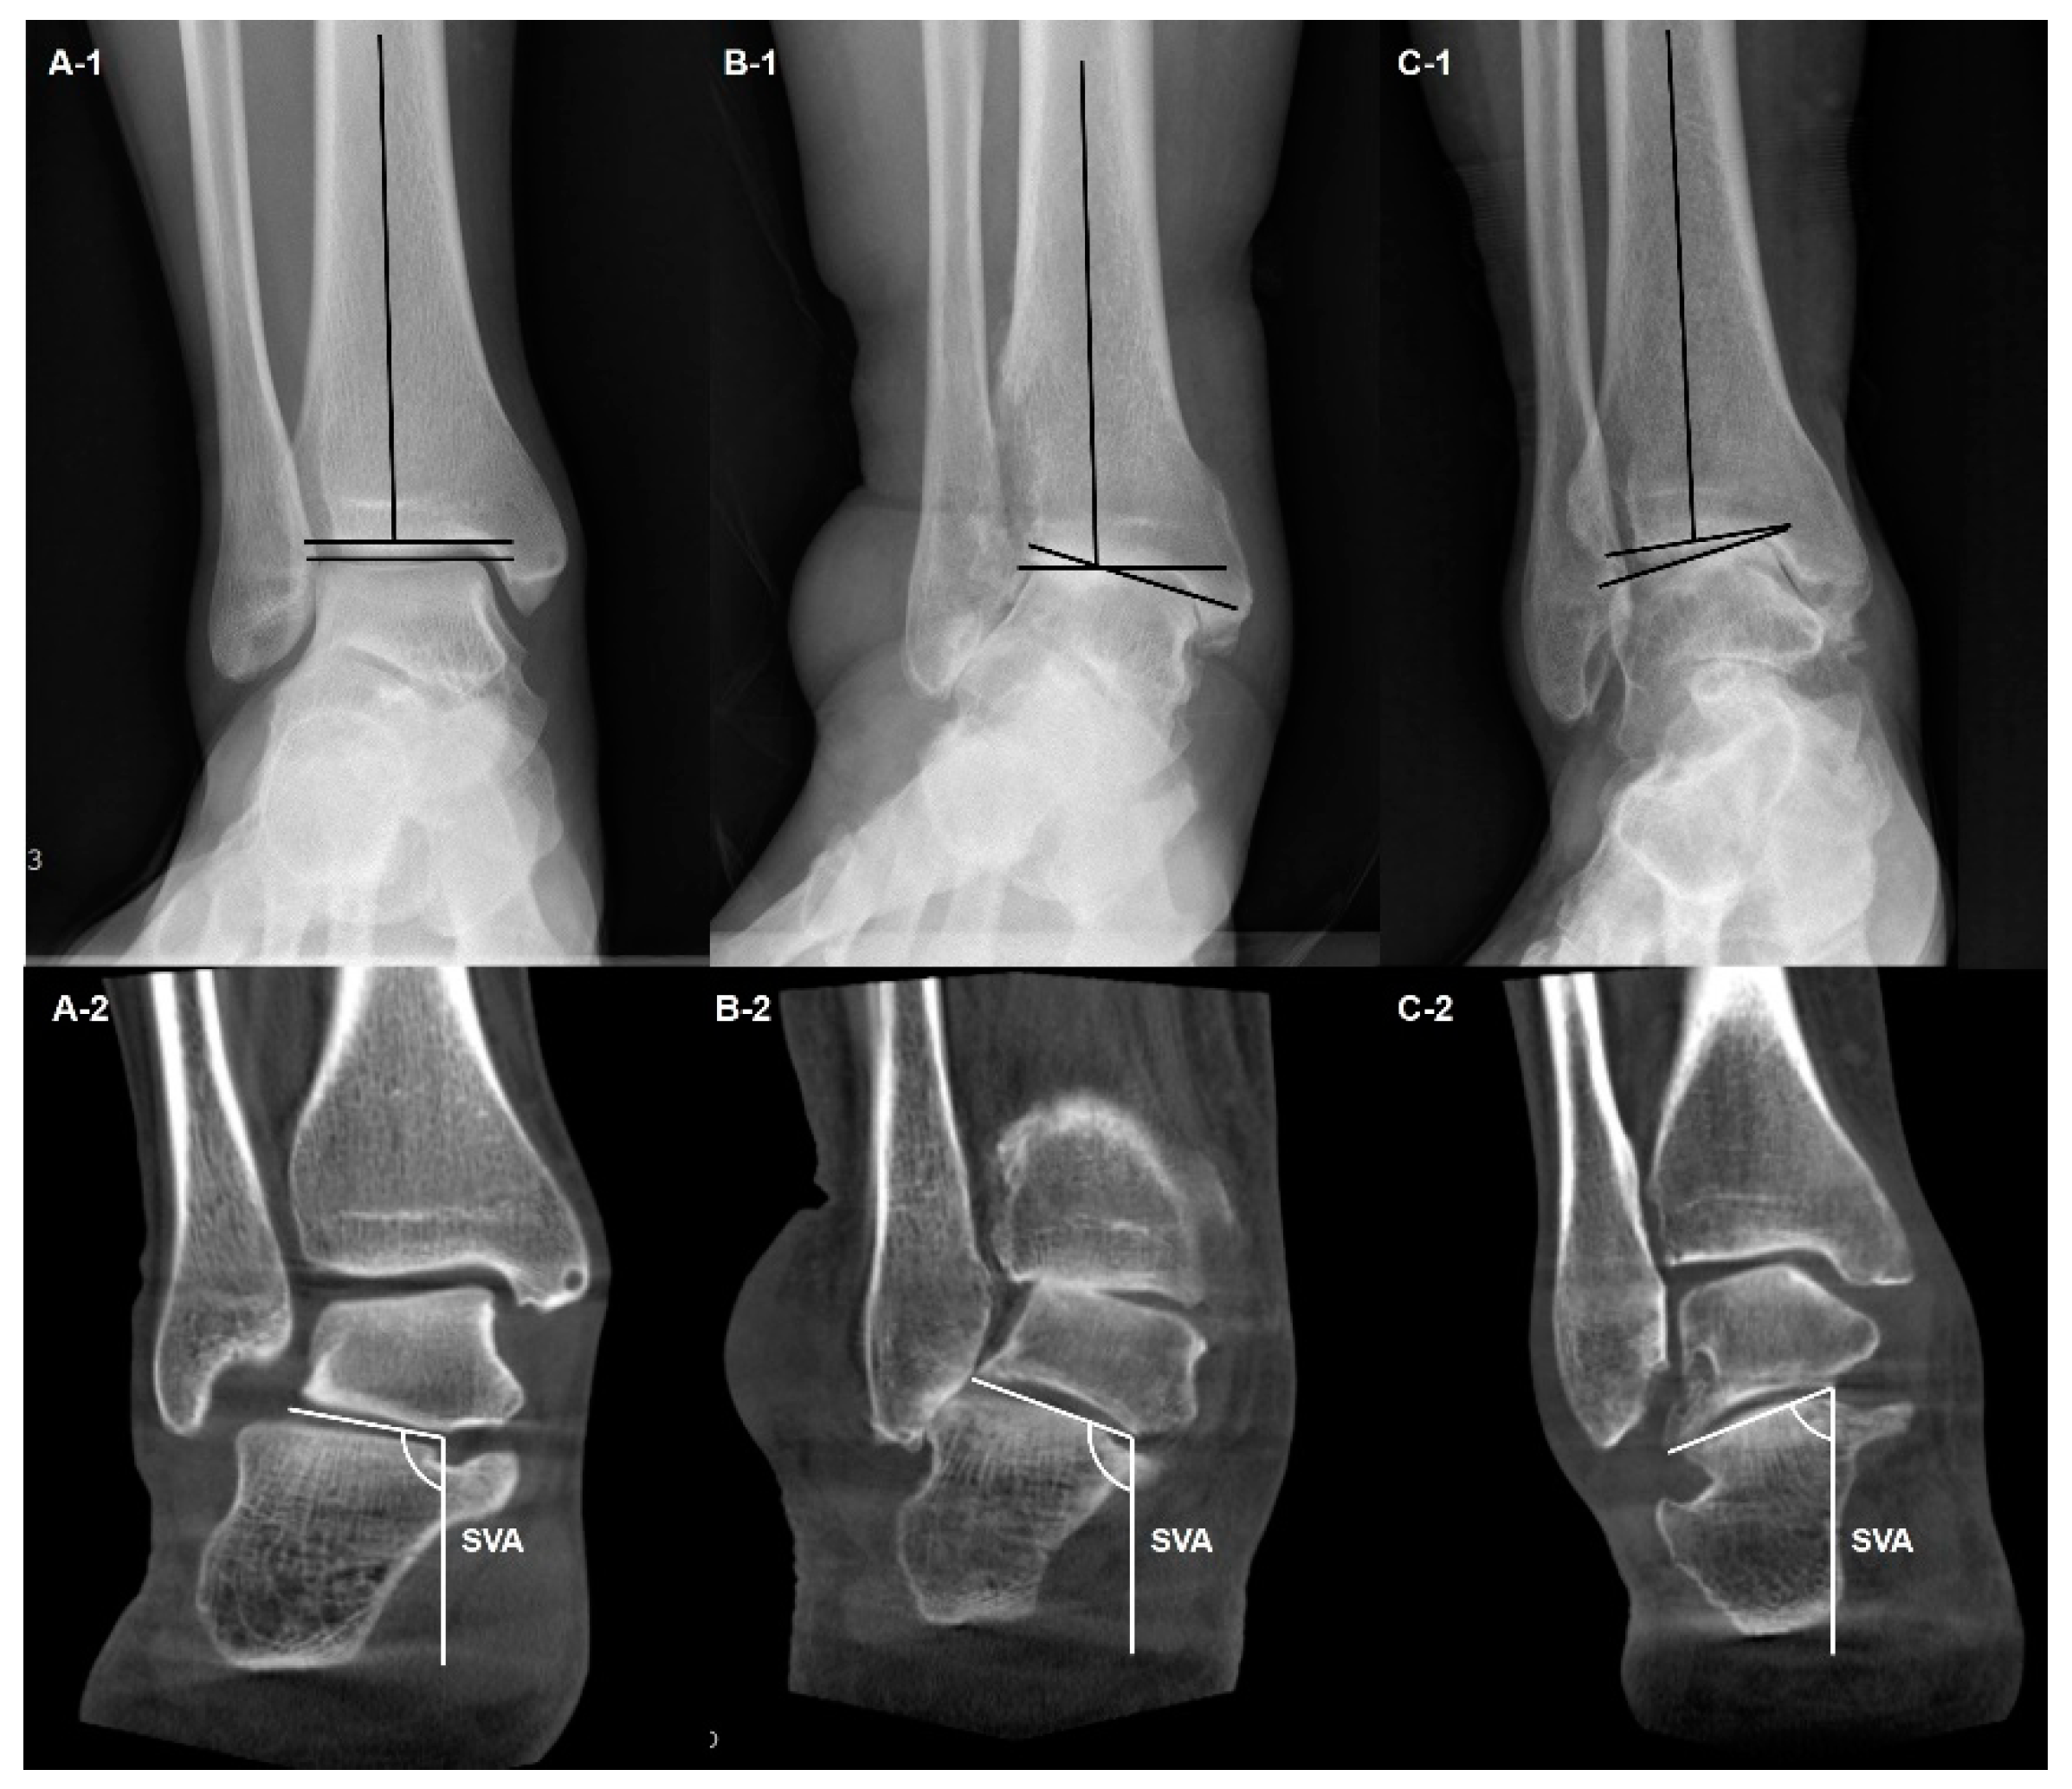

- Kang, H.W.; Kim, D.Y.; Park, G.Y.; Lee, D.O.; Lee, D.Y. Coronal plane Calcaneal-Talar Orientation in Varus Ankle Osteoarthritis. Foot Ankle Int. 2022, 43, 928–936. [Google Scholar] [CrossRef]